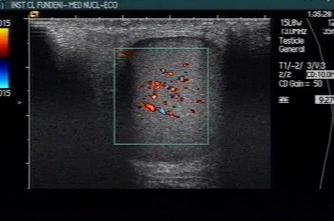

• Studiul opacifierii ramurilor corticale ale arterelor cerebrale medii (M4) drepte și stângi și a venelor cerebrale interne drepte și stângi (Fig.1).

Fig.1 ACTMS cranio-cerebrală, recon MIP în plan axial (a,b) și sagital (c): aspect normal; (a) opacifierea arterelor temporale dreaptă și stângă (săgeţi); (b) opaciferea ramurilor corticale ale arterelor cerebrale medii (M4)-săgeţi albe; opaciferea venelor cerebrale interne dreaptă și stângă (săgeţi negre-b și c).

Semiologie:

▶ Absența opacifierii M4 = 1 punct

▶ Opacifierea M4 = 0 punct

▶ Absența opacifierii venei cerebrale interne = 1 punct

▶ Opacifierea venei cerebrale interne = 0 puncte

• Un scor egal sau mai mare de 3 confirmă stopul circulator intracerebral. In acest caz, concluzia examinării este: „stop circulator intracerebral” care vine în sprijinul diagnosticului clinic de moarte cerebrală sau aspect ACT compatibil cu moartea cerebrală

• În caz contrar, concluzia examinării este „absența opririi circulatiei intracerebrale”, situaţie în care diagnosticul clinic de MC nu este confirmat.